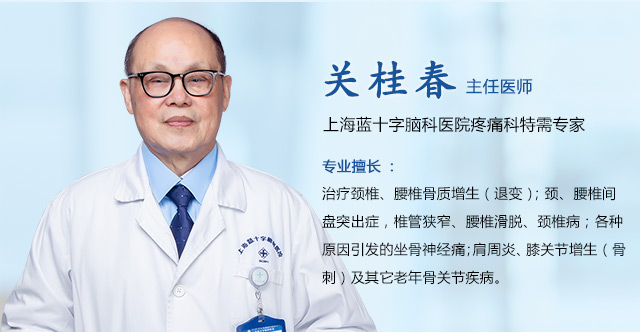

上海蓝十字脑科医院肿瘤科(放疗)主任王晓东表示,人体鼻咽部结构复杂,具有呼吸、吞咽、防御保护等功能,当肿瘤侵及相应组织和神经时,可引发复杂多样的临床症状。

上海蓝十字脑科医院肿瘤科(放疗)主任、副主任医师王晓东:由于鼻咽部的位置特殊,采取传统手术切除肿瘤方式有一定局限性,难度高,风险较大,术后容易快速复发。但近年来,我国对鼻咽癌临床研究不断深入,形成了《中国鼻咽癌放射治疗指南》(以下简称“指南”),为鼻咽癌诊治的临床决策提供了更多的循证证据。

王晓东主任郑重提醒,早发现、早诊断、早治疗是提高鼻咽癌患者预后的关键。一旦确诊鼻咽癌,尽早进行放疗干预,不仅可有效控制癌细胞扩散转移,甚至有治愈的可能,可显著提高患者的生存期和生活质量。

▲ 上海蓝十字脑科医院引进了瑞典医科达

Synergy数字化直线加速器